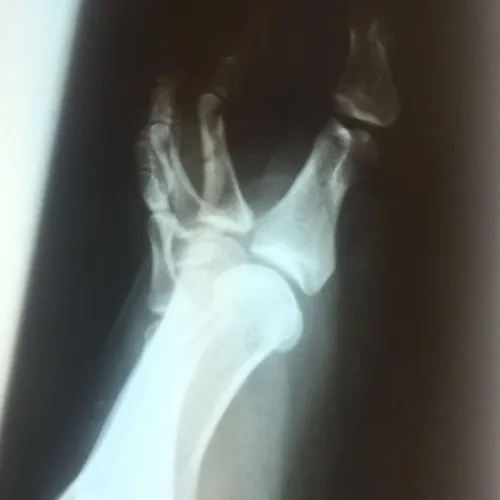

Patient had chronic pain after comminuted sesamoid fracture. After conservative care, patient had total sesamoidectomy and is pain free 3 months postop

Pre and Postop Tibial Sesamoidectomy